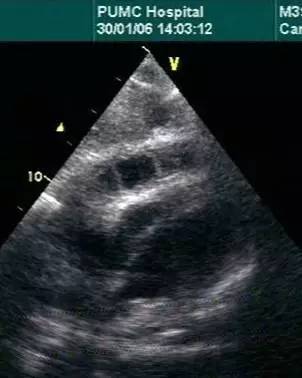

超声心动图

对心包厚度识别不是优势

cardiac tamponade and pulsus paradoxus